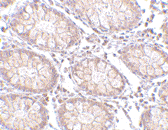

Below: Immunohistochemistry of PTK7 in human colon tissue with PTK7 antibody at 5 µg/ml.